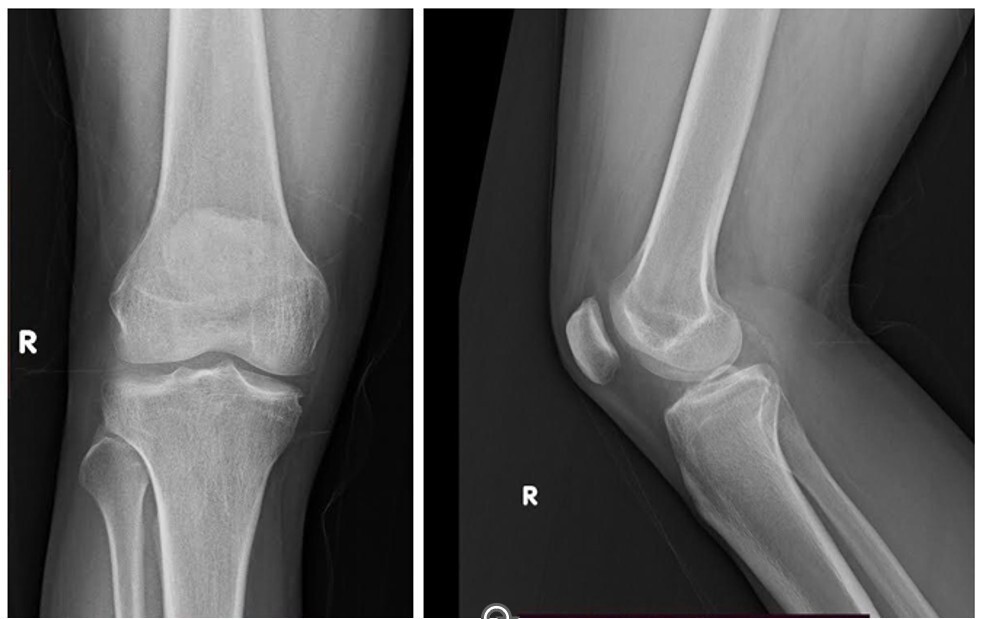

Radiographs demonstrated a subtle radio-opaque circular shadow located just posterior to the tibial slope (Fig. 1). T2-weighted MRI imaging revealed a well-defined lesion with heterogeneous signal intensity, measuring 1.4 × 2.5 × 3 cm. The lesion was situated in the midline posterior compartment, anterior to the knee capsule, and in close proximity to the posterior cruciate ligament (PCL) (Fig. 2). The differential diagnoses included ganglion cyst, Baker’s cyst, parameniscal cyst, PVNS, lipoma arborescens, synovial hemangioma, early-stage SC, and soft-tissue neoplasms such as synovial sarcoma or chondrosarcoma. The patient underwent a computed tomography torso and chest radiograph, which revealed no evidence of primary malignancy or metastasis.

Figure 1: Plain radiograph of the knee showing a subtle radio-opaque circular shadow located just posterior to the tibial slope, suggestive of an intra-articular or para-articular lesion.